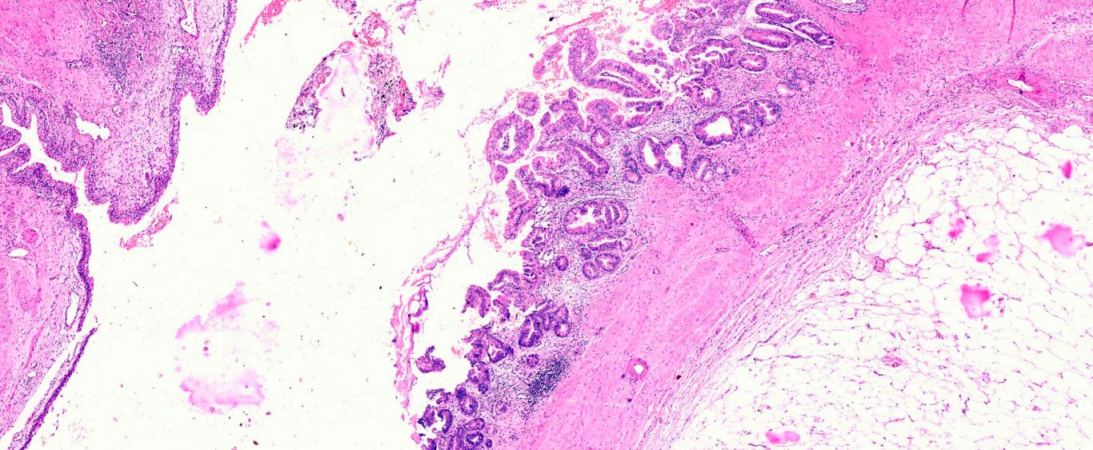

A 31-year-old male of Asian-Indian origin presented to the outpatient department with a one-year history of dull aching right-sided flank pain. There were associated symptoms of abdominal distension and difficulty in voiding urine for the same duration. There was no history of polyuria, graveluria, hematuria or dysuria. On examination, right costovertebral angle tenderness was noted. General and systemic examinations were unremarkable. No lymphadenopathy was noted. On investigation, complete blood count and liver and renal function tests were within normal limits. Urine microscopy showed increased pus cells (20–30/high power field); there were no red blood cells, casts, crystals or malignant cells. Ultrasonography of kidney, ureter and bladder region revealed right-sided hydronephrosis. Computed tomography (CT) scan revealed a hyperdense mass of 2.3x4.6 mm in the right renal pelvis with severe hydronephrosis and cortical thinning (Figure 1 [Fig. 1]). Renal dynamic scan revealed a poorly functioning right-sided kidney. Considering the poor functional status, right-sided nephrectomy was performed and the specimen was sent for histopathological examination. On gross examination, the kidney measured 11x8x5 cm with a cut surface showing dilated pelvicalyceal system filled with slimy watery fluid; the renal pelvis was thickened with a greyish-white cut surface. Multiple stones were noted in the pelvis and kidney parenchyma. Microscopic examination revealed features of chronic pyelonephritis; the adjacent renal pelvis showed pseudostratified columnar epithelial metaplasia with presence of tumor cells arranged in the form of glands and suspended in mucin pools. The tumor infiltrated lamina propria and superficial layers of the muscle coat of the renal pelvis (Figure 2 [Fig. 2], Figure 3 [Fig. 3], Figure 4 [Fig. 4], Figure 5 [Fig. 5]). Adenocarcinoma in situ was noted in the adjacent ureter (Figure 6 [Fig. 6]). Pathological TNM staging was pT2aNxMx.

Figure 2: Scanner view showing mucinous adenocarcinoma involving the renal pelvis (H&E, 20X)